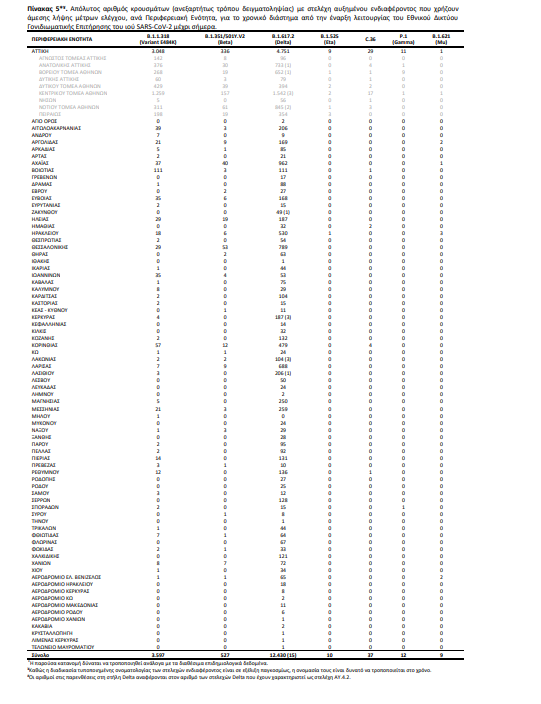

Πίνακας 5. Απόλυτος αριθμός κρουσμάτων (ανεξαρτήτως τρόπου δειγματοληψίας) με στελέχη αυξημένου ενδιαφέροντος που χρήζουν άμεσης λήψης μέτρων ελέγχου, ανά Περιφερειακή Ενότητα, για το χρονικό διάστημα από την έναρξη λειτουργίας του Εθνικού Δικτύου Γονιδιωματικής Επιτήρησης του ιού SARS-CoV-2 μέχρι σήμερα